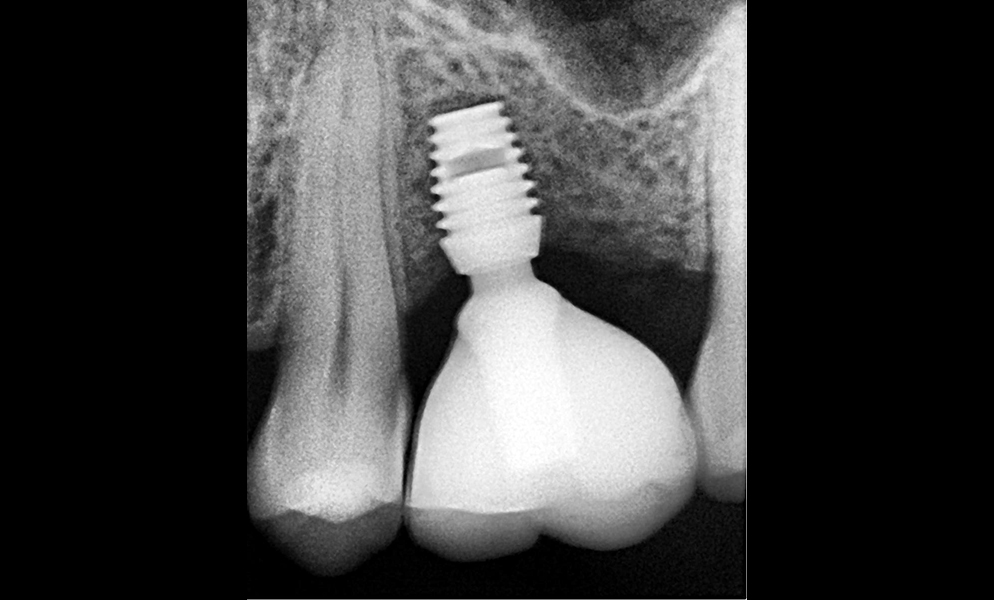

| Before | After |

![]() |

| Single posterior tooth missing space restored with a 5x5 mm short dental implant (Bicon, USA) to avoid sinus lift and bone graft procedures | |